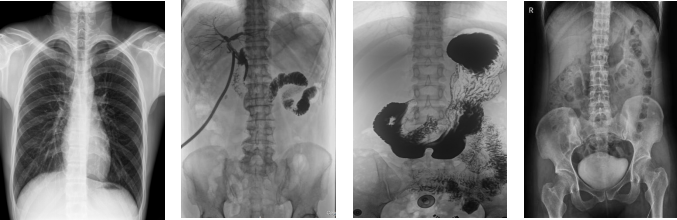

PLD8000C數字胃腸DR機全面突破傳統X射線攝影透視理念,成像部件采用新型動態(tài)平板探測器,輕松解決數字攝影、數字透視、數字造影等功能,并使數字透視獲得超大尺寸和清晰的圖像效果。滿足放射科、體檢中心、影像中心、內科、婦科、外科、急診科、骨科、創(chuàng)傷科、消化科等科室的各種臨床檢查需求。如果您想采購這款數字胃腸DR機,歡迎咨詢400-025-6366。